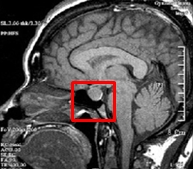

뇌수종